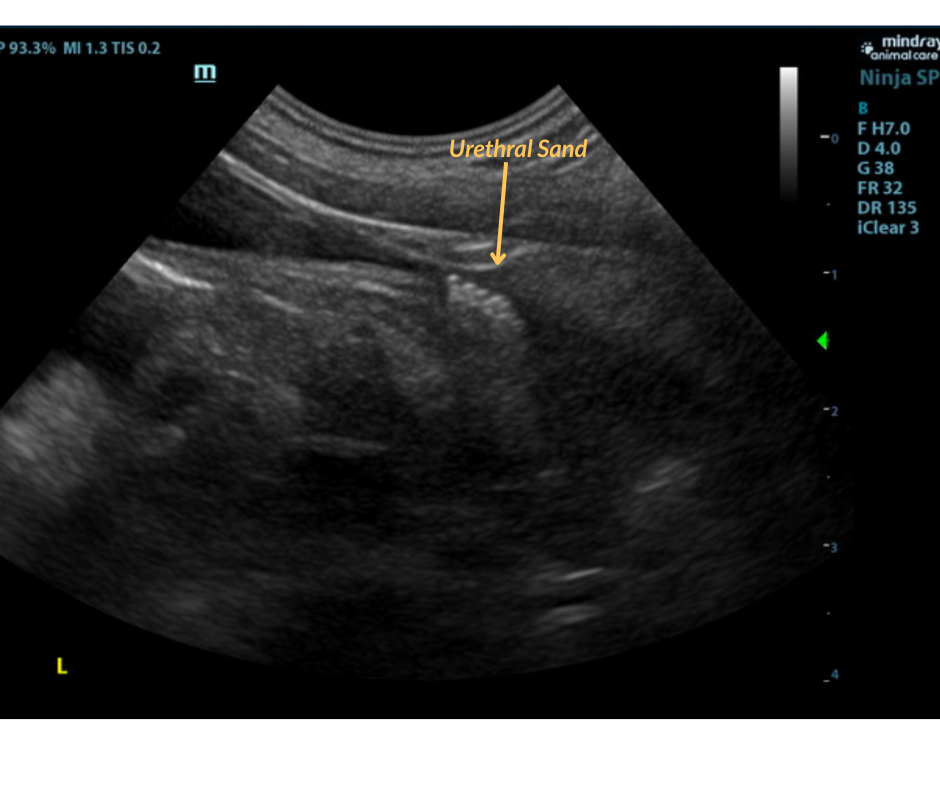

Urinary System:

The urinary bladder and visible pelvic urethra were unremarkable for the level of repletion presented.The urine, however, did present some mildly echogenic debris consistent with mucous, exfoliated cells from renal or bladder origin, and/or blood clots as these echogenic changes can all present similarly. A minor amount of urethral sand was noted just prior to the prostate. The prostate measured 1.5 cm. The kidneys were both swollen with hypervascularity. This is likely owing to abnormal ammonia metabolism. The right kidney measured 5.33 cm. The left kidney measured 5.16 cm. Both testicles were retained and were inguinal and extra-abdominal.

- Bladder sand and debris.